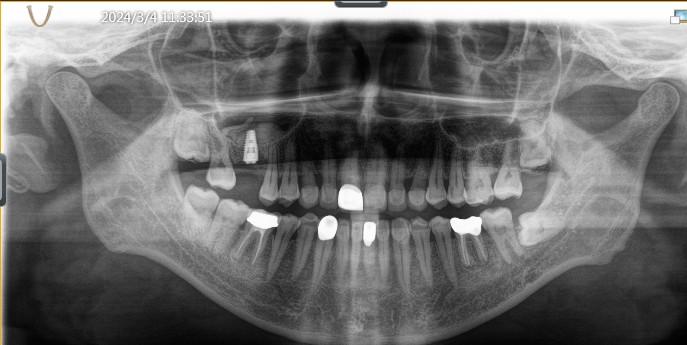

拔牙后半年复诊影像学检查

综合考虑患者自愿选择欧种植体。最终16 植入 4.8*10mm ITI 种植体,由于垂直高度不足,腭侧骨缺损区植入bio-oss骨粉0.25g及CGF,并盖bio-Gide膜及CGF膜,严密缝合。 二期三期如期进行。余近日戴牙。

术后照片